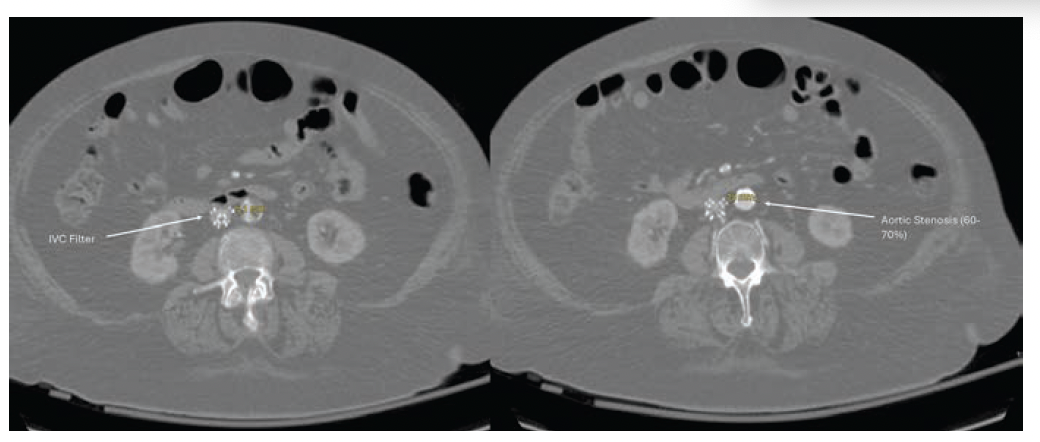

Approximately 1.5 years prior to consultation, the patient’s ankle-brachial indices were measured at 0.46 on the right and 0.24 on the left. Given her significant comorbidities and frailty, the patient was deemed unsuitable for further revascularization at that time by another department. However, her persistent and severe ischemic pain continued to be a major concern for the patient and her family. A CT angiogram (CTA) was obtained at our institution through another department, with the aim of identifying potential revascularization targets that could alleviate her symptoms. The CTA revealed severe diffuse bilateral vascular disease, including 60% to 70% stenosis of the distal aorta, severe stenosis of the right common femoral artery, occlusion of a right profunda-to-popliteal bypass graft and occluded native right superficial femoral artery, an occluded or severely stenotic right popliteal artery, and 2-vessel runoff to the right foot via the posterior tibial and peroneal arteries (Figures 1 and 2). On the left, there was multifocal mild-to-moderate disease in the common and proximal external iliac arteries, a patent external iliac stent, long-segment occlusion of the left superficial femoral artery, and 2-vessel runoff to the left foot via the posterior tibial and peroneal arteries (Figure 3).